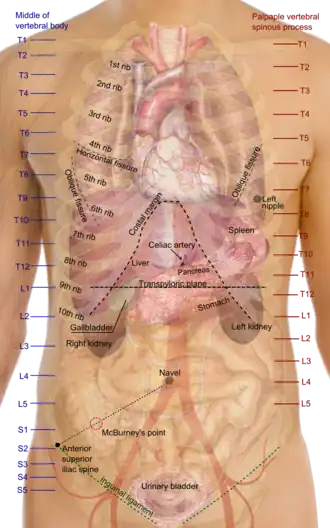

In some of its facets human anatomy is closely related to embryology, comparative anatomy and comparative embryology,[1] through common roots in evolution; for example, much of the human body maintains the ancient segmental pattern that is present in all vertebrates with basic units being repeated, which is particularly obvious in the vertebral column and in the ribcage, and can be traced from very early embryos.

Surface anatomy

Surface anatomy, or superficial anatomy, is the study of anatomical landmarks that can be identified readily from the contours or other reference points on the surface of the body.[1] It is important in human anatomy: with knowledge of superficial anatomy, physicians gauge the position and anatomy of deeper structures.

Common names of parts of the human body, from top to bottom:

- Head – face – forehead – jaw – cheek – chin

- Neck – shoulder

- Arm – elbow – wrist – hand – finger – thumb

- Spine – chest

- Abdomen – groin

- Hip – buttocks – leg – thigh – knee – calf – ankle – foot – heel – toe

- Eyes, ears, nose, mouth, teeth, tongue, throat, Adam's apple, breasts, penis, scrotum, vulva, and navel are also superficial structures.